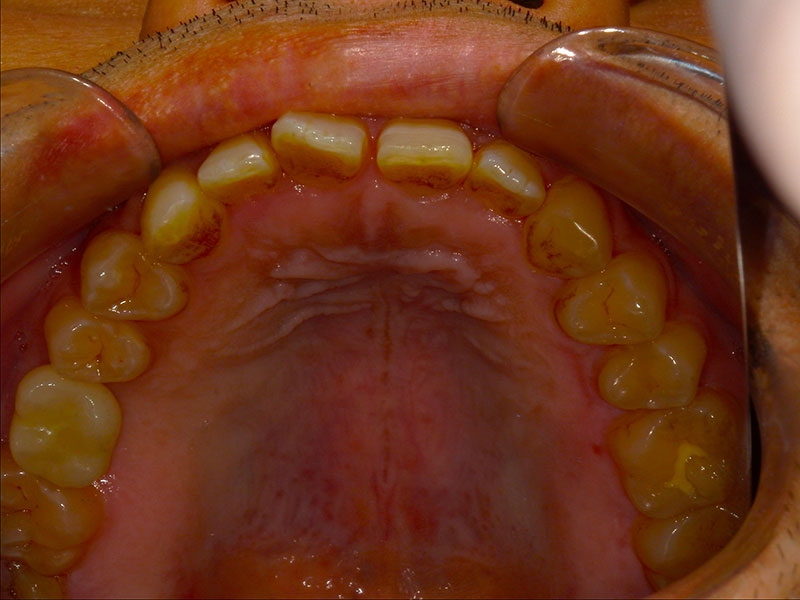

患者様は35歳、男性の方で、主訴としては患者様から何か訴えるということはなかったです。元々を言えば、他の歯の治療やクリーニングで来院されていたのですが、口腔内を診察させていただきましたところ、右上の奥歯(右上6)が崩壊していて、根っこだけの状態であったのですが、特に痛みなどはなくずっと放置していたとのことでした。私から食事をする時など食べにくくないか聞いたところ、ずっと前から気になっていて今回を機会に治療したいとの申し出がございました。

レントゲン写真およびCT画像なのですが、右上6が残歯状態であり歯根破折を起こしている状態でした。しかし歯槽骨から上顎洞底までの距離は十分に認められます。この歯槽骨から上顎洞までの距離がないとソケットリフトなどのオプションの処置が必要になってくるのですが、今回の症例では大掛かりな処置の必要はなく症例の難易度としては比較的イージーな方でした。上顎洞などに関して知りたい方はこちらのページを参照にしていただければと思います。